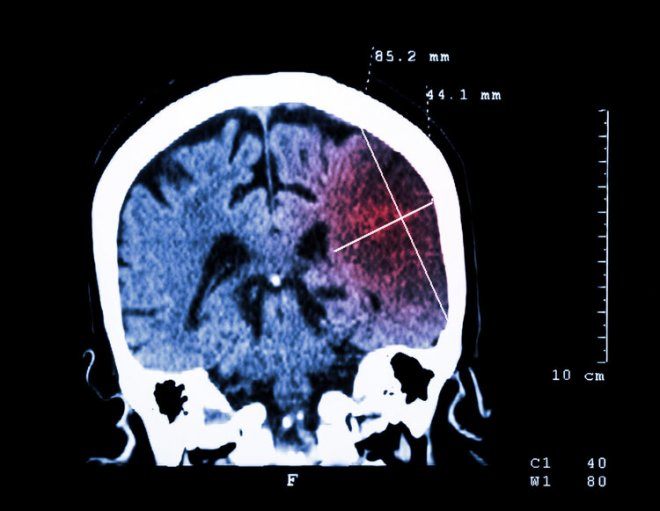

一行人將他送到醫院檢查,原來徐師傅竟是患上了腦梗塞,好在送來的及時經過搶救已經脫離了危險。

腦梗死,又稱缺血性中風,占腦中風患者總數的60%~70%。《柳葉刀•神經學》期刊發布的「全球疾病負擔研究」數據顯示,1990~2017年近30年間,中風一直高居 居民死亡原因榜首,情況不容樂觀。

《腦卒中防治報告(2018)》指出,40歲及以上人群腦卒中現患人數達1242萬,每年196萬人因腦卒中死亡。卒中學會發布的流行病學數據顯示,每年新發病例高達330萬人。